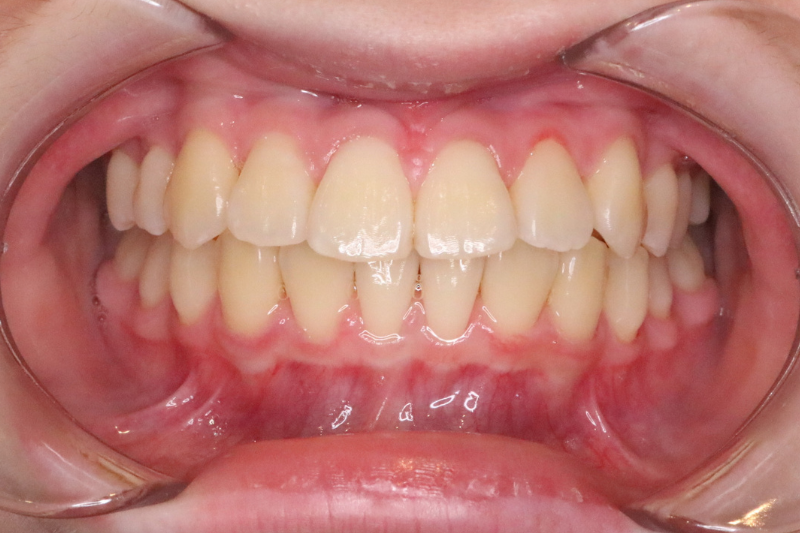

症例4

Before

症例4 治療前

After

症例4 治療後

年齢・性別 10歳・女の子

治療内容 インビザラインファースト

治療期間 1年7ヶ月

費用 400,000円(税込)

主なリスク 矯正装置の装着時に違和感や痛みが生じる場合があります。

装置の使用状況により治療期間が延長する場合があります。

治療後、保定装置を使用しない場合は後戻りする可能性があります。

治療結果には個人差があります。